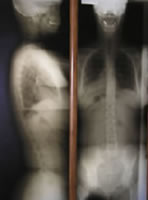

通常のレントゲン写真と違うことは、背骨のすべてを上から下まで撮影できるようになっていることで、直立した状態(重力が普通に加えられた状態)で撮影します。ガンステッドカイロプラクティックは、このレントゲン撮影が重要な役割を果たします。

レントゲン写真によって患者さんの脊椎のすべての状態を、視覚で確認することができます。これは姿勢、関節、椎間板の整合性、椎骨のズレ、治療できない病変(禁忌)、最近の骨折を評価するのに役に立ちます。